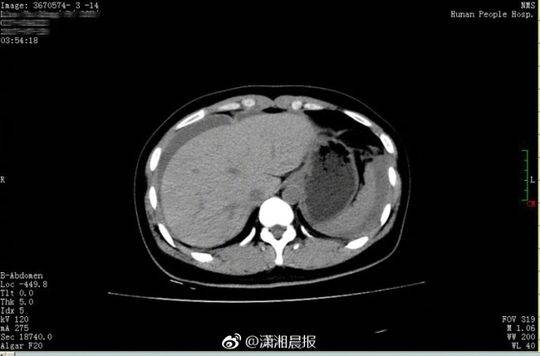

26 歲的小晴和28 歲的小東是一對新婚夫婦,因工作的緣故兩地分居。8 月16 日,近半年未見丈夫的小晴回到長沙。晚上,小別勝新婚的兩人免不了親熱一番。誰知激情過后,小晴出現下腹部疼痛,而且越痛越厲害,只得來到湖南省人民醫院天興閣院區急診科就診。尿妊娩檢查結果為陰性,而腹部CT 提示盆腔、腹腔有大量積血、積液,隨即轉入婦科。黃薇副主任醫師接診后發現,小晴面色蒼白,渾身大汗淋漓,脈搏為102 次/ 分,呼吸22 次/ 分,血壓89/54mmgH, 血紅蛋白為79g/l, 已達到失血性休克的標準。

黃薇立即為小晴進行診斷性腹腔鏡手術,術中發現腹腔內積血約1500ml,接近她全身總血量的40%," 再晚一點來,就會危及生命了"。醫生還發現,在她右側卵巢有一個直徑3cm 左右的黃體囊腫表面有破口,破口有血塊附著,還有活動性出血。黃薇立即為她施行黃體囊腫剝除和創面縫合止血手術,恢復了卵巢的正常形態。